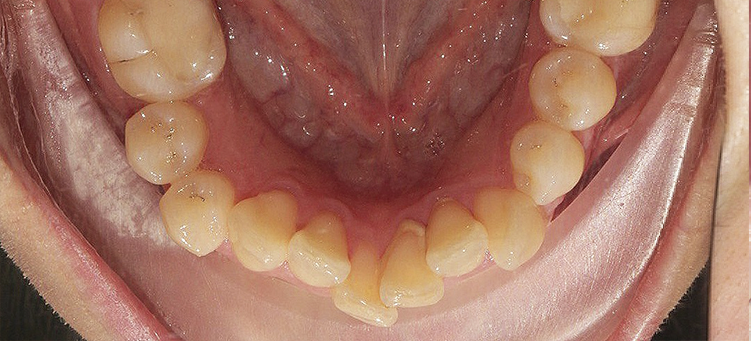

Исправления скученности верхних и нижних резцов